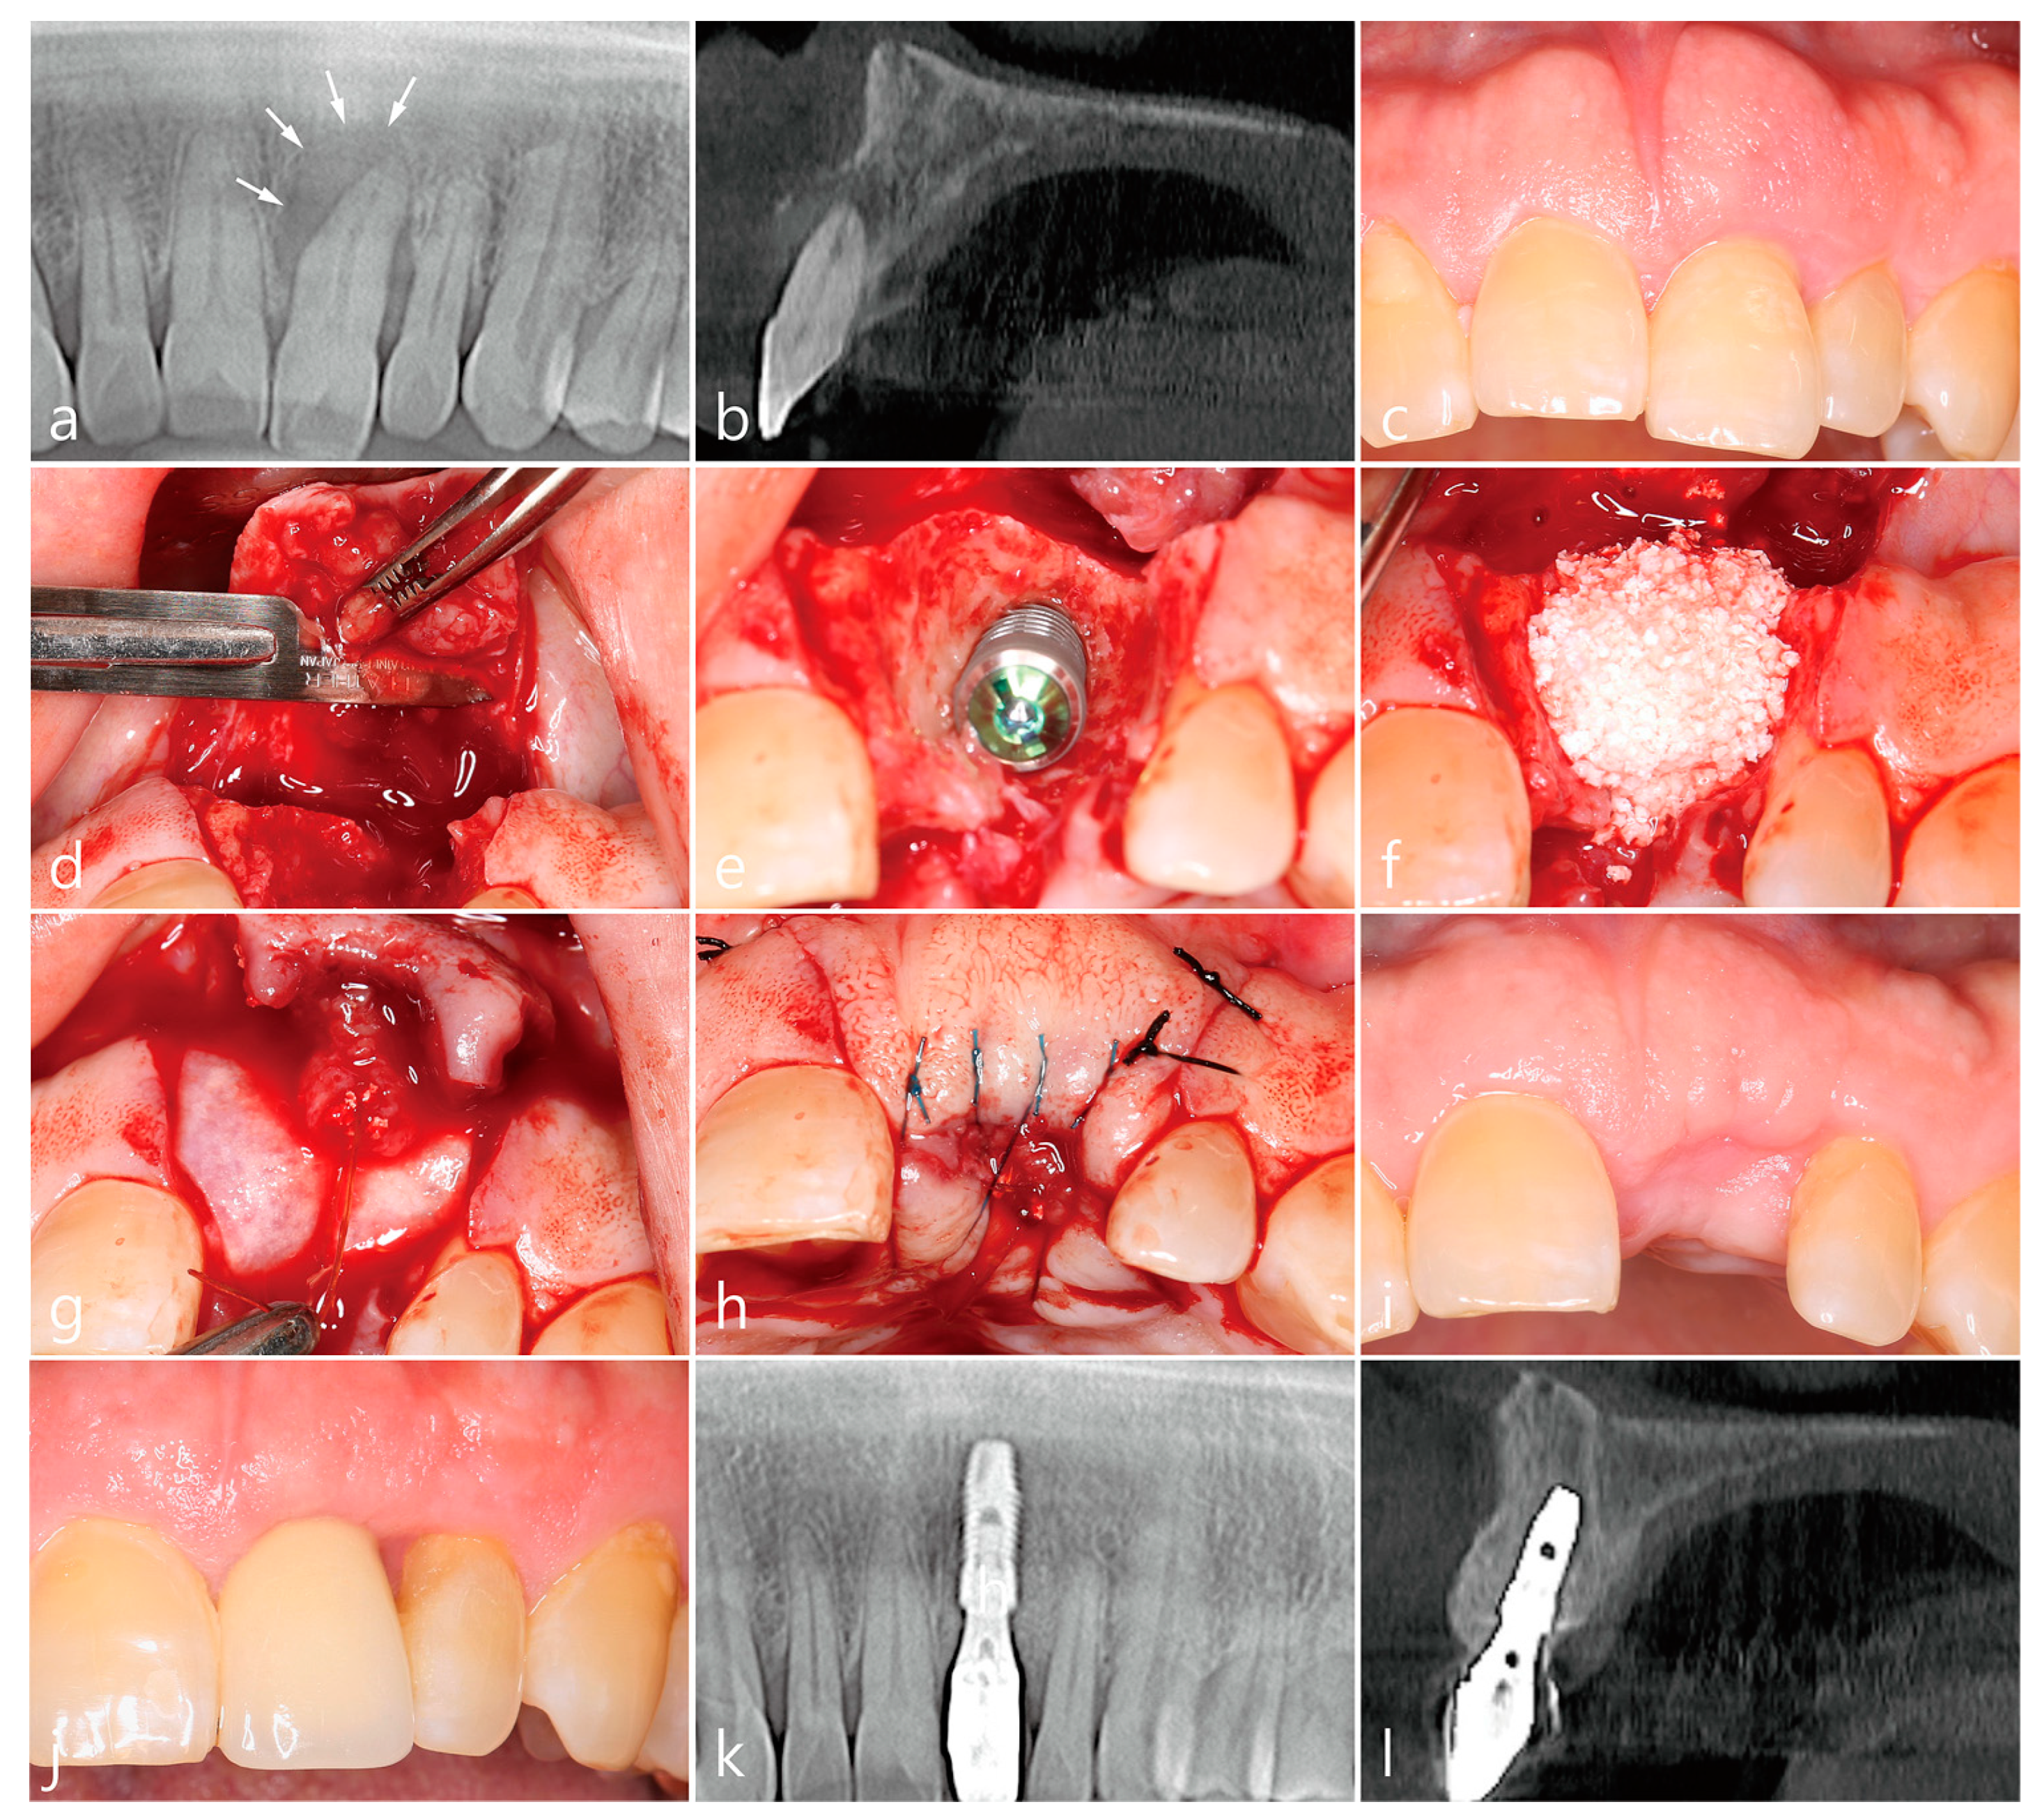

3. Case 1

- A tooth or implant with severe bone loss was removed using extraction forceps under local anesthesia with 2% lidocaine containing 1:100,000 epinephrine;

- A midcrestal incision and two buccal vertical incisions were made. Before raising the flap, special care was taken to ensure a clean dissection of the IGT from the underlying flap without any damage and the IGT is still well-attached to the flap. The IGT was then further separated from the bony housing by using a curette with various curvatures and a periosteal elevator.

- The IGT attached to the buccal flap was dissected to an appropriate thickness using a #15 blade so that the base of the IGT was still attached to the existing flap, and the flap was eventually extended. Periosteal releasing incisions were not performed at the flap base.

- The extraction socket was thoroughly debrided using a Molt curette and a titanium brush.

- A surgical guided stent was used so that the implant (Implantium, Dentium, Suwon, Korea) was placed 2.0 mm subcrestal to the level of the adjacent bone in the extraction socket.

- A synthetic osteoconductive bone graft substitute composed of hydroxyapatite (HA) and beta-Tricalcium phosphate (β-TCP) (Osteon III, Genoss, Suwon, Korea) and a resorbable collagen membrane (Genoss, Suwon, Korea) were placed to cover the implant and the peri-implant osseous defect.

- After covering the bone graft with the collagen membrane, the extended IGT was sutured with the palatal flap with 4-0 Catgut. Next, the buccal flap was closed using 4-0 nylon or black silk.